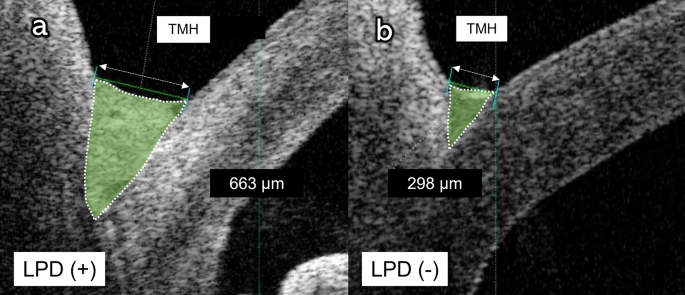

Among 127 eyes, 12 (9.4%) eyes from nine patients (mean age: 77.11 ± 3.07 years [range, 71–81 years]; four women, five men) had LPD based on the lacrimal irrigation test. None of the patients with conjunctivochalasis and entropion showed LPD. The mean TMH was significantly higher in the LPD group than in the non-LPD group (494.9 ± 263.7 μm vs. 292.8 ± 130.0 μm, P = 0.007; Table 2; Fig. 2).

The mean TMH in patients with and without LPD were 494.9 ± 263.7 μm and 292.8 ± 130.0 μm, respectively. Recent studies have used SS AS-OCT to measure TMH and detect LPD. TMH before and after lacrimal surgery has been reported to be 448–707 μm and 253–340 μm, respectively, consistent with our findings18,19,25. Specifically, TMH in the non-LPD group did not significantly differ from that after lacrimal duct surgery in previous reports. We found that TMH was significantly higher in the LPD group than in the non-LPD group (Fig. 4), which is consistent with previous reports that TMH was significantly higher in patients with LPD than in healthy participants14,25,26,27. We observed a significant association of TMH with LPD, which suggests that TMH measurement using AS-OCT before cataract surgery can facilitate the prediction of the presence of LPD.

TMH measurements were performed using swept-source (SS) AS-OCT (CASIA2; Tomey, Tokyo, Japan). Vertical line scans through the corneal center were performed before lacrimal irrigation and pupil dilation. TMH was manually evaluated and defined as the distance between the lower eyelid–meniscus junction and the upper cornea–meniscus junction on the AS-OCT images. TMH was automatically calculated using built-in software (Fig. 5).